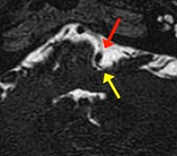

赤矢印が顔面痙攣の原因となる責任血管(椎骨動脈)で、脳幹から顔面神経の移行部(黄色矢印)を圧迫することで痙攣を引き起こしています。

画像所見通り、責任血管(椎骨動脈)(赤色矢印)が顔面神経(黄色矢印)を圧迫しており、責任血管を顔面神経から引き離すことにより痙攣が消失します。